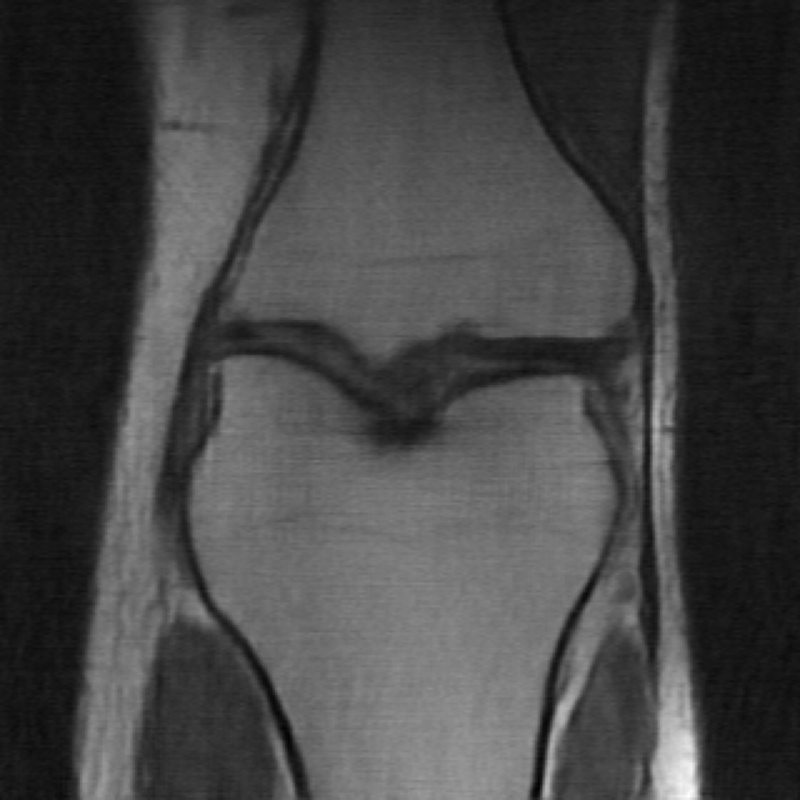

MRI reconstruction is performed with a undersampling of k-space in the phase encoding direction for both and . The sampling maps are shown in Fig 4.

![]() |

| (a) Original k-space sampling pattern () | (b) Resampled k-space sampling pattern () |

The data used in the undersampled MRI experiments were obtained from the NYU fastMRI Initiative [45]. The primary goal of the fastMRI dataset is to test whether machine learning can aid in the reconstruction of medical images. We trained and tested on a subset of the single-coil knee dataset, which consist of simulated single-coil measurements. In all tests, we use complex-valued data, which interfaces with our deep networks by treating the real and imaginary parts of the images as separate channels. We measure reconstruction accuracy with respect to the center 320320 pixels of the complex IFFT of the fully-sampled k-space data. For the purpose of visualization, we display only the magnitude images in the following sections.

In the case of MRI, we use two choices of , depending on whether we assume is fully known or not. In the case is fully known, we utilize another undersampled k-space mask, but with resampled high-frequency lines. We display the original and new k-space sampling masks in Figure 4. To illustrate the utility of our approach under miscalibration of the forward model in an MRI reconstruction setting, we also consider a unknown random perturbation of the original k-space lines, which we attempt to learn during reconstruction. The vertical k-space lines are still fully sampled, as are the center 4 of frequencies, but all high frequency lines are perturbed uniformly at random with a continuous value from -2 to 2. We wish to emphasize that this experiment is not meant to reflect clinical practice, since such miscalibration of k-space sampling locations is not typically encountered in anatomical imaging with Cartesian k-space sampling trajectories. However, we include this experiment simply to illustrate that our approach could be extended to unknown parametric changes in the forward model in an MR reconstruction setting.